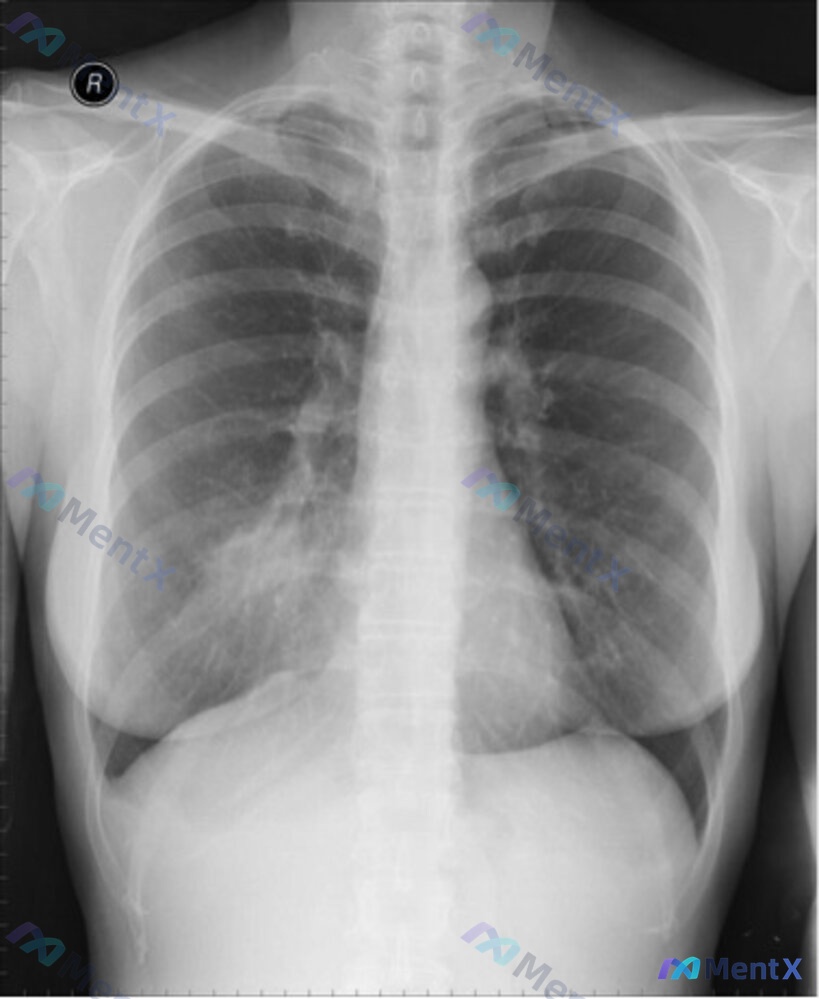

已拍胸部正侧位X光片,影像表现重点:

- 正位:右肺中叶区域片状密度增高影,边界尚清,边缘模糊渗出

- 侧位:病灶位于心影前缘后方,右肺中叶解剖位置,呈楔形致密影,未见明确空洞

- 其余肺野、肺门、心影、纵隔、胸膜腔等未见明显异常